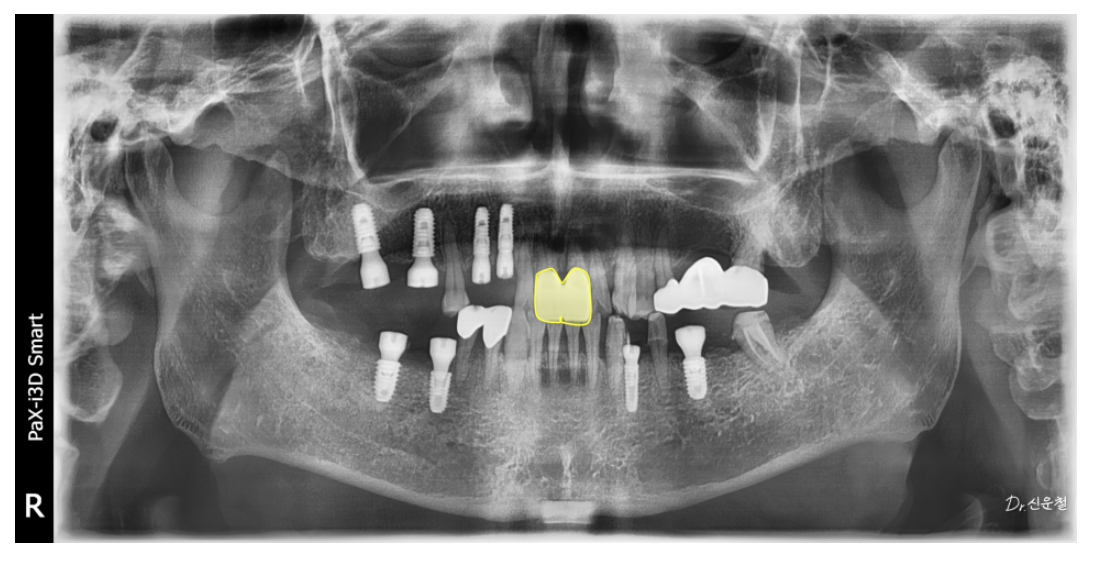

2단계: 정출된 치아는 발치 후 임플란트로 교정

이미 많이 내려온 치아는

되돌리기보다 발치 후 임플란트로 위치를 재정렬하는 것이 안정적이었습니다.

최종 결과: 전체 균형을 다시 회복

임플란트와 보철 치료가 모두 자리 잡은 뒤

다시 촬영한 사진에서는

✓ 양쪽으로 균형 있게 씹을 수 있는 교합

✓ 앞니·어금니의 힘 분산 안정

✓ 정출·기울기 문제 해결

이 확인되었습니다.